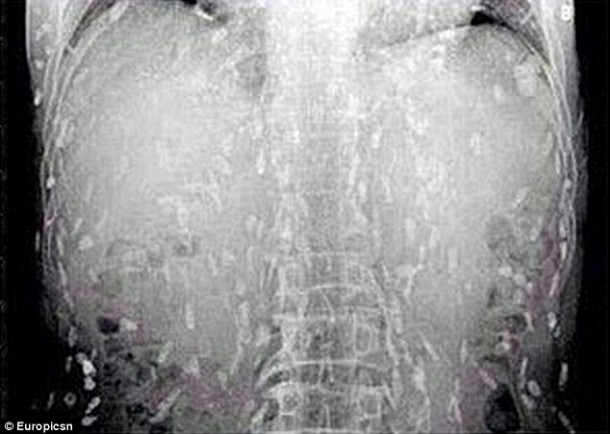

Sur place, le médecin lui fait passer des radiographies pour identifier la cause de son mal-être. Les radiographies révèlent que l’homme a des larves de ténia dans tout le corps. Le Dr Yin, a indiqué que l’homme « avait probablement mangé du poisson cru contaminé par des oeufs ». C’est à cela que l’homme doit son infection parasitaire. Si son cas n’avait pas été traité rapidement, l’homme aurait pu mourir. En effet, lorsque l’infection atteint le cerveau, cela peut se révéler mortel.